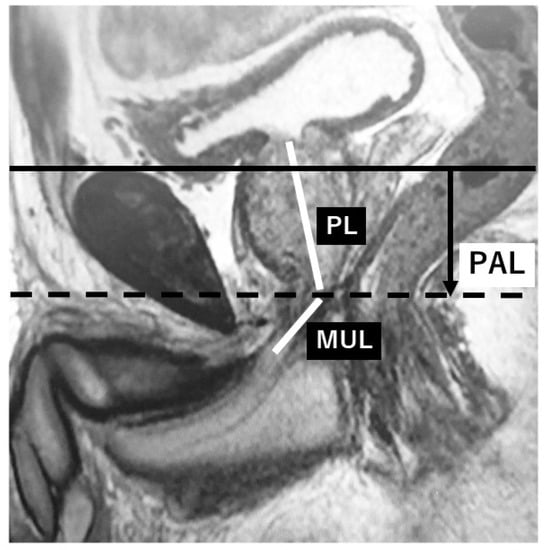

Among 285 consecutive patients with prostate cancer who underwent RALP at our hospital between March 2013 and December 2017, 270 patients were included in this study. These 270 patients had complete records of preoperative data including MRI and postoperative outcomes, and received postoperative follow-up for more than 3 months. Patients with a neurogenic bladder or end-stage kidney disease were not included. Preoperative MRI parameters consisted of the membranous urethral length (MUL), prostate length (PL), and pubic symphysis-prostate apex length (PAL) on sagittal images. PAL was defined as the distance between the extension lines of the suprapubic ridge line and the prostate apical line on sagittal MRI (Figure 1), which indicates the anatomical location of the vesico-urethral anastomosis after RALP.

Figure 1. Preoperative parameters on sagittal MRI. (PL: Prostate length, MUL: Membranous urethral length, PAL: Pubic symphysis-prostate apex length, solid line: Extension line of the suprapubic ridge line, dotted line: Extension line of the prostate apical line.).

In this study, we defined PAL as the distance between the extended lines of the suprapubic ridge line and the prostate apical line on sagittal MRI, which may indicate the vesico-urethral anastomosis site at prostatectomy, i.e., the bladder neck location defined on postoperative cystograms. We hypothesized that the shorter the PAL, the higher the vesico-urethral anastomosis site, and this condition subsequently leads to the earlier recovery of urinary incontinence. This study showed that the location of the bladder neck on postoperative cystograms could be predicted preoperatively by evaluating PAL using sagittal MRI. MUL was not a factor predicting the location of the bladder neck on postoperative cystograms. Furthermore, as reported previously [4], the higher the position of the bladder neck, the earlier that urinary continence was achieved (p < 0.001). An independent predictive factor, however, for the urinary continence status at three months after RALP was MUL based on preoperative sagittal MRI from multivariate analysis. PAL, which was a predictive factor for the location of the bladder neck on postoperative cystograms, may also be a predictive factor for urinary continence at three months, although it was not significant (p = 0.06). As mentioned above, there were some discrepancies in that the predictive factor for the location of the bladder neck on postoperative cystograms was not significantly correlated with the predictive factor for the three-month urinary continence status.